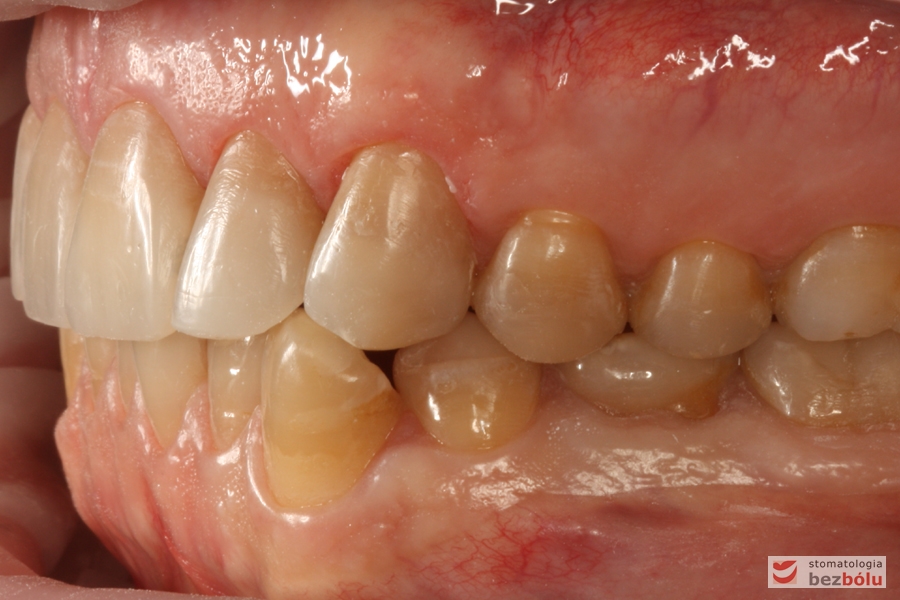

Zęby w zwarciu - strona prawa, przebarwienia świadczące o chorobie szkliwa (hypoplazja)

Zęby w zwarciu – strona prawa, przebarwienia świadczące o chorobie szkliwa (hypoplazja)

Zęby w zwarciu - strona lewa, kieł w zgryzie krzyżowym i znacznie starte zęby boczne

Zęby w zwarciu – strona lewa, kieł w zgryzie krzyżowym i znacznie starte zęby boczne